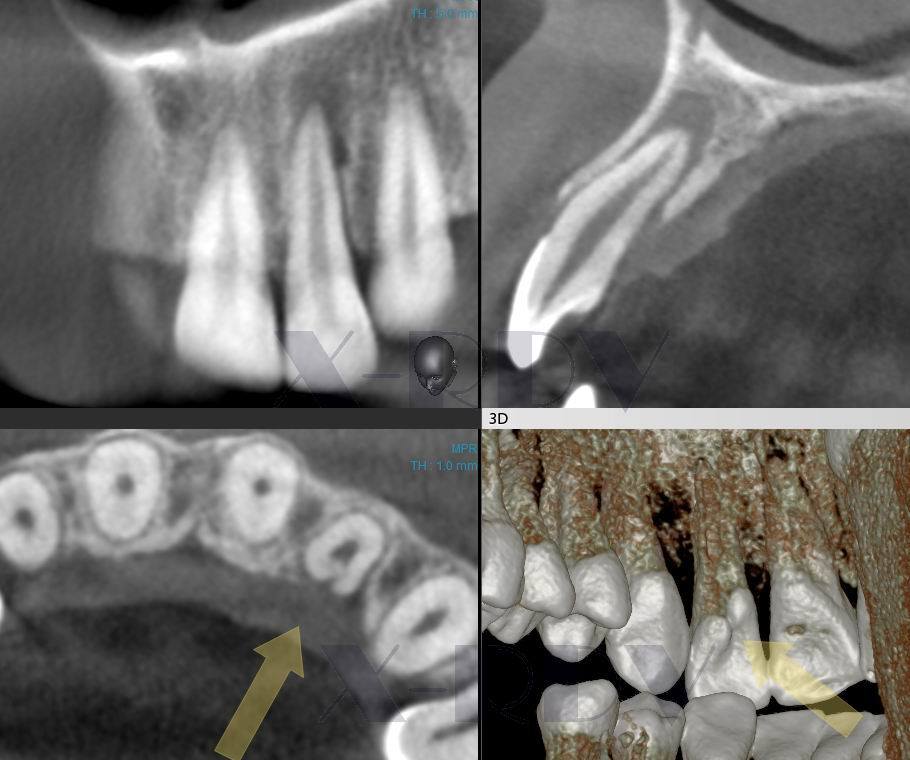

Рентгеновские снимки кариеса корня зуба

Раздел: Визуальные уроки